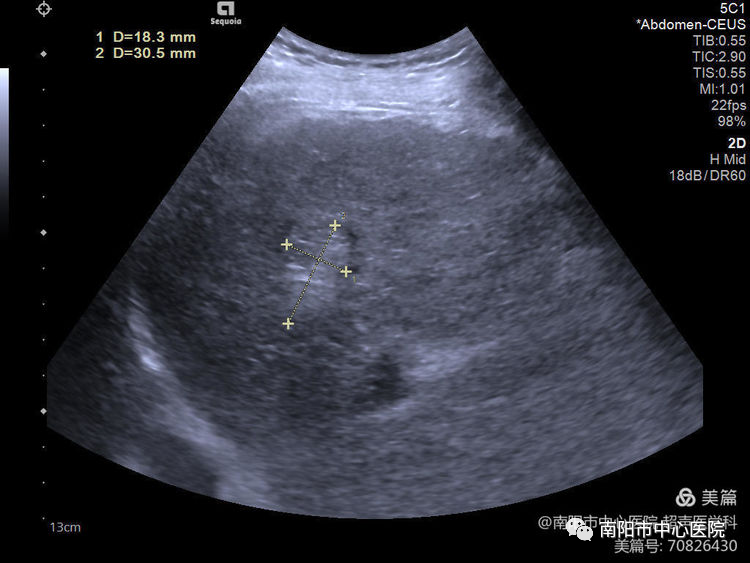

術(shù)前常規(guī)超聲探查,腫瘤位于肝S8,大小約31*20*18mm,周邊可見肝中靜脈、門脈右前支包繞。